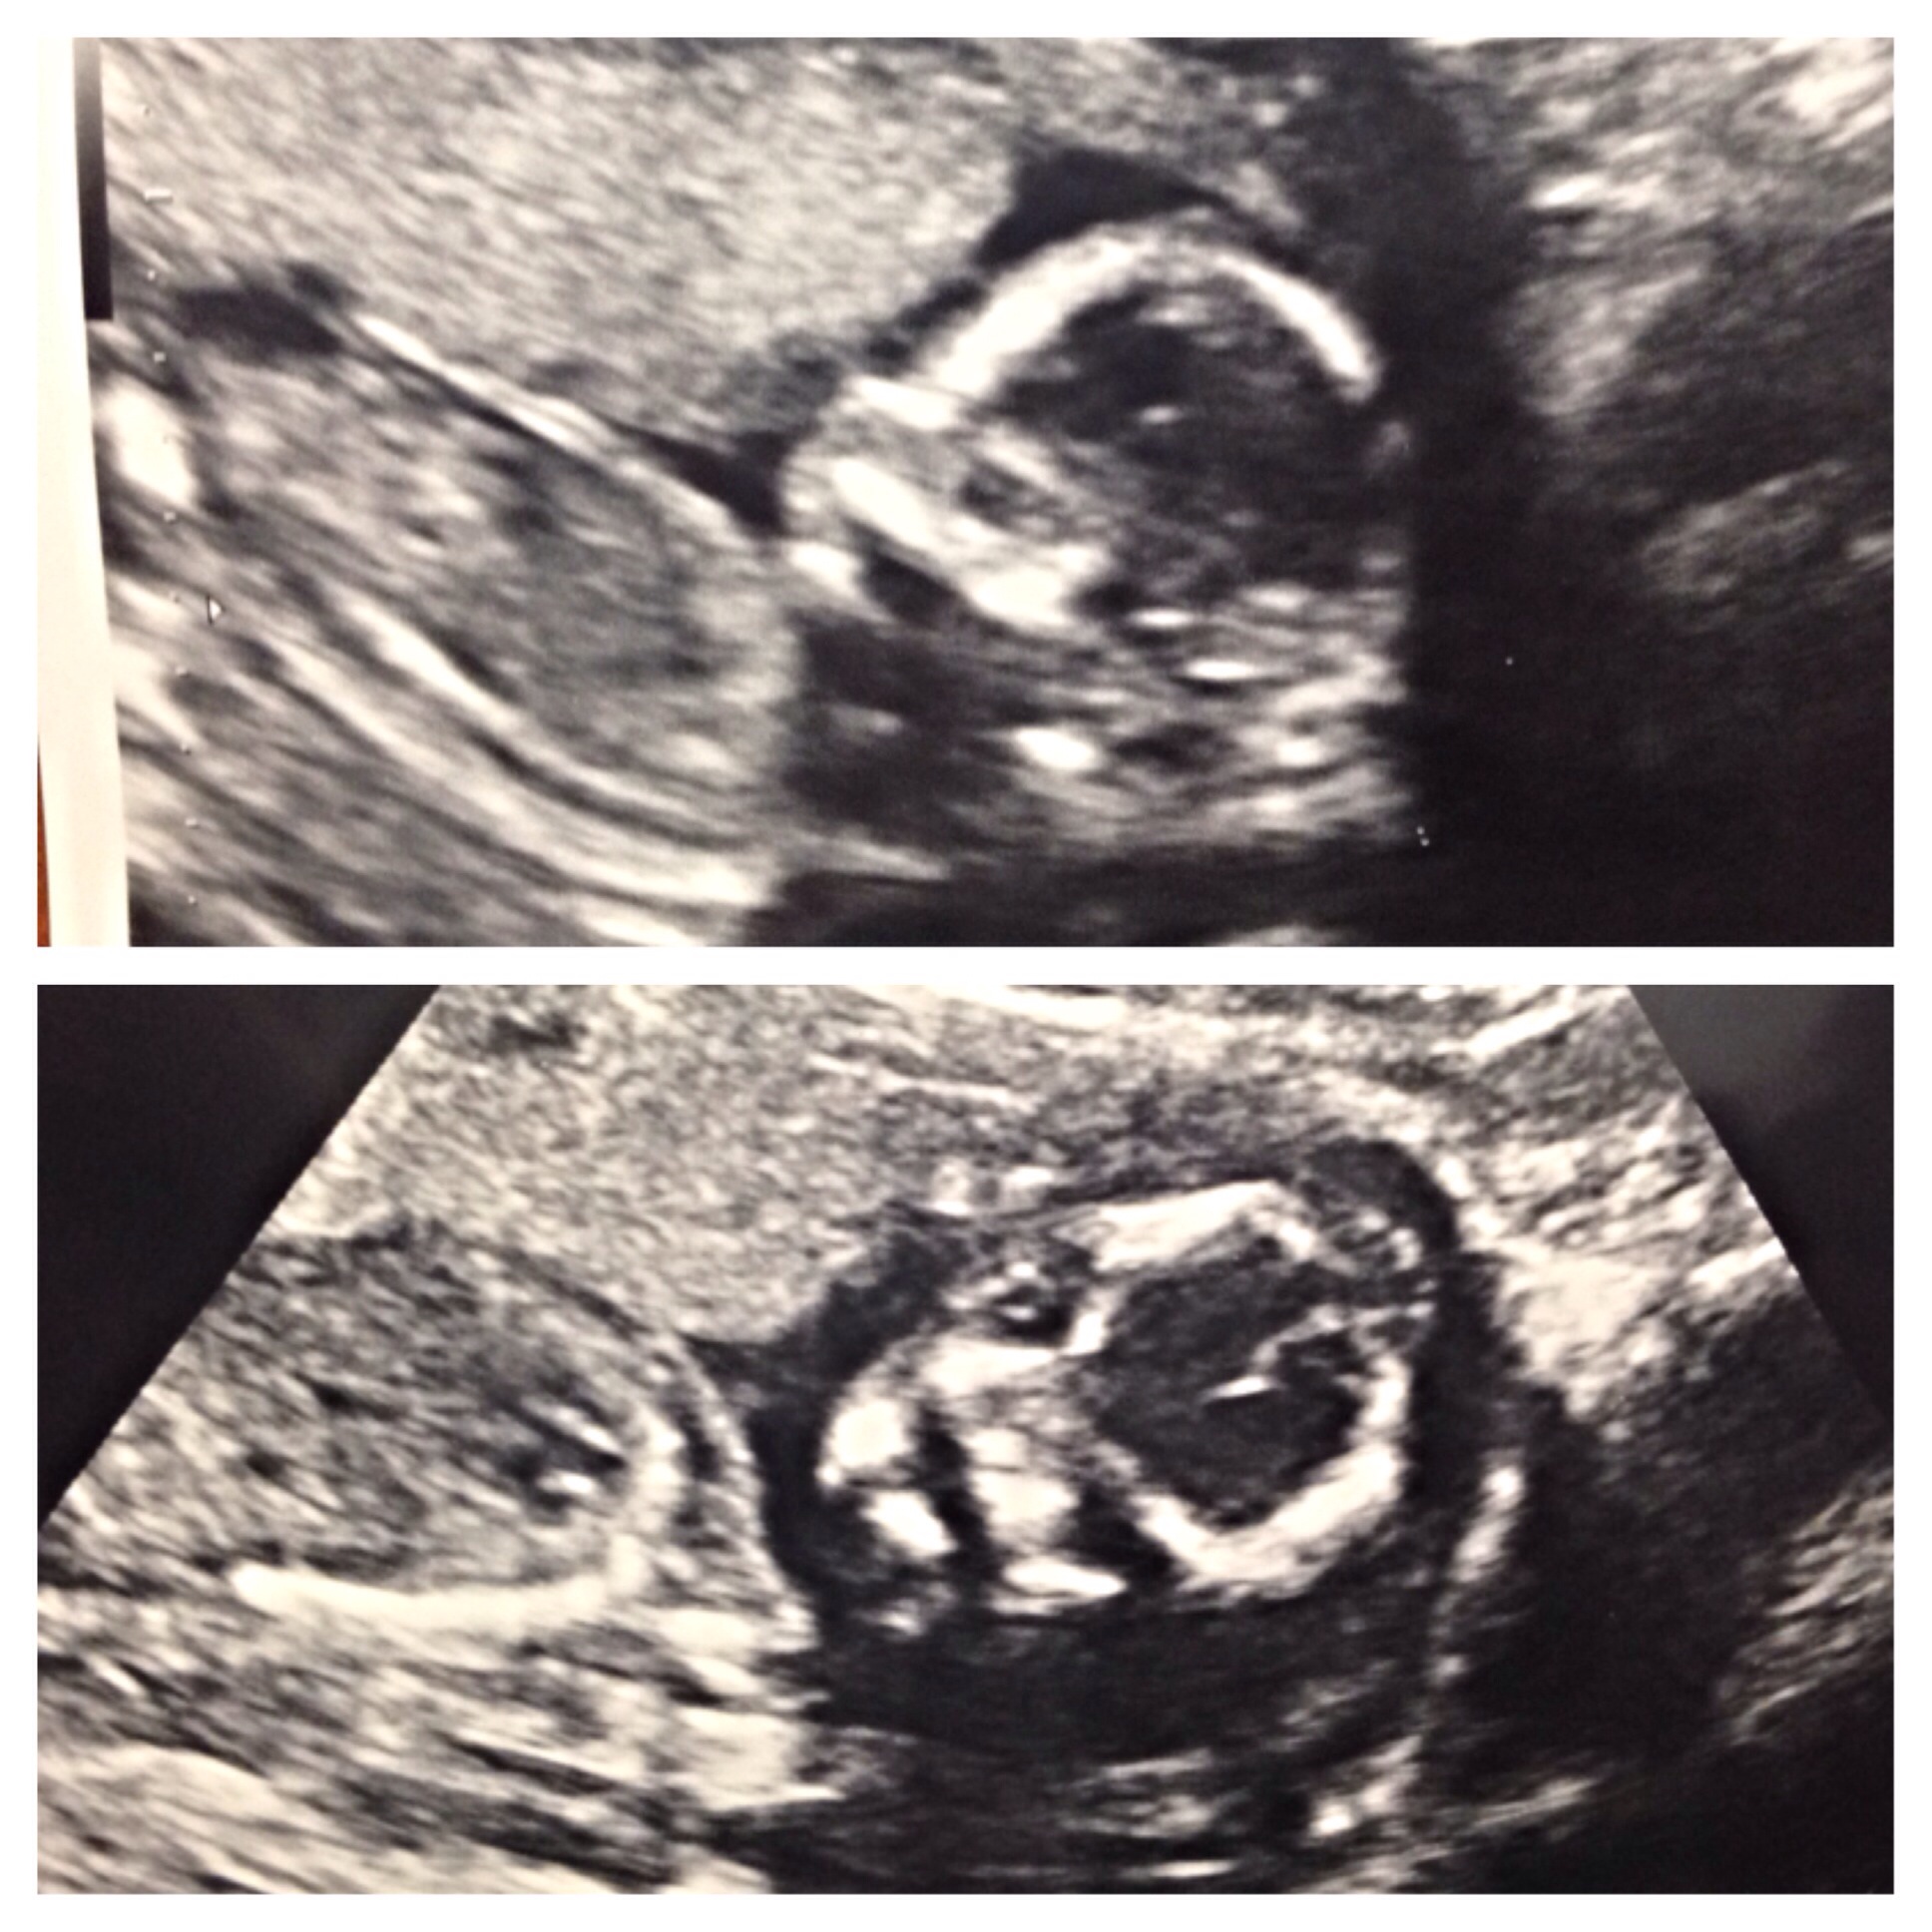

Ultrasound Today! Boy or Girl?

They said it's too early to tell... I'm 13w5d